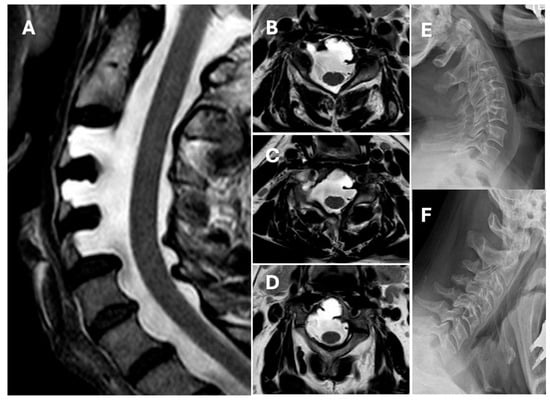

We present the case of a 62-year-old male patient with no significant medical history who underwent ENT evaluation for nasal polyposis. A computed tomography (CT) scan of the cervical spine revealed large defects of the posterior wall of the vertebral bodies of C3, C4, and C5. The magnetic resonance imaging (MRI) scan revealed that the dural sac filled with cerebrospinal fluid occupied the defects. Post-contrast imaging did not reveal signs of bony rearrangement, vascular malformations, or tumors. CT head imaging did not reveal signs of lateral ventricle dilation, and the lumbar puncture performed showed no increase in cerebrospinal fluid pressure. Additionally, dynamic X-rays of the cervical spine in maximum flexion and extension did not reveal spinal instability (Figure 1). Genetic testing did not identify any mutations associated with either NF1 or KFS. Since there are no other known genetic conditions associated with ACM, further genetic testing was not recommended. A neurological evaluation found no focal deficits, while the patient denied pain.

Figure 1.

Illustrative case. (A) Magnetic resonance imaging (MRI) T2-weighted sagittal scan showing C3, C4, and C5 anterior cervical meningocele. (B) MRI T2-weighted axial scan showing C3 anterior meningocele. (C) MRI T2-weighted axial scan showing C4 anterior meningocele. (D) MRI T2-weighted axial scan showing C5 anterior meningocele. (E) Dynamic lateral X-ray scan of the neck in maximum extension and (F) in maximum flexion does not show signs of cervical instability.